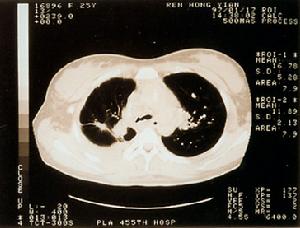

氣管、支氣管狹窄1、x 線氣管斷層攝片可發現狹窄氣管。

雙側支氣管嚴重狹窄對本病的預防主要是早期發現、早期診斷、早期治療原發性疾病,對發生在氣管及支氣管的病變應考慮到造成氣道狹窄的可能性,提前預防氣道狹窄病變的發生。在檢查時,氣管碘油造影檢查雖對診斷氣管狹窄及瞭解狹窄範圍均有價值,但有加重氣管梗阻的危險,值得注意。除非在其它檢查手段均無法明確診斷時不使用。